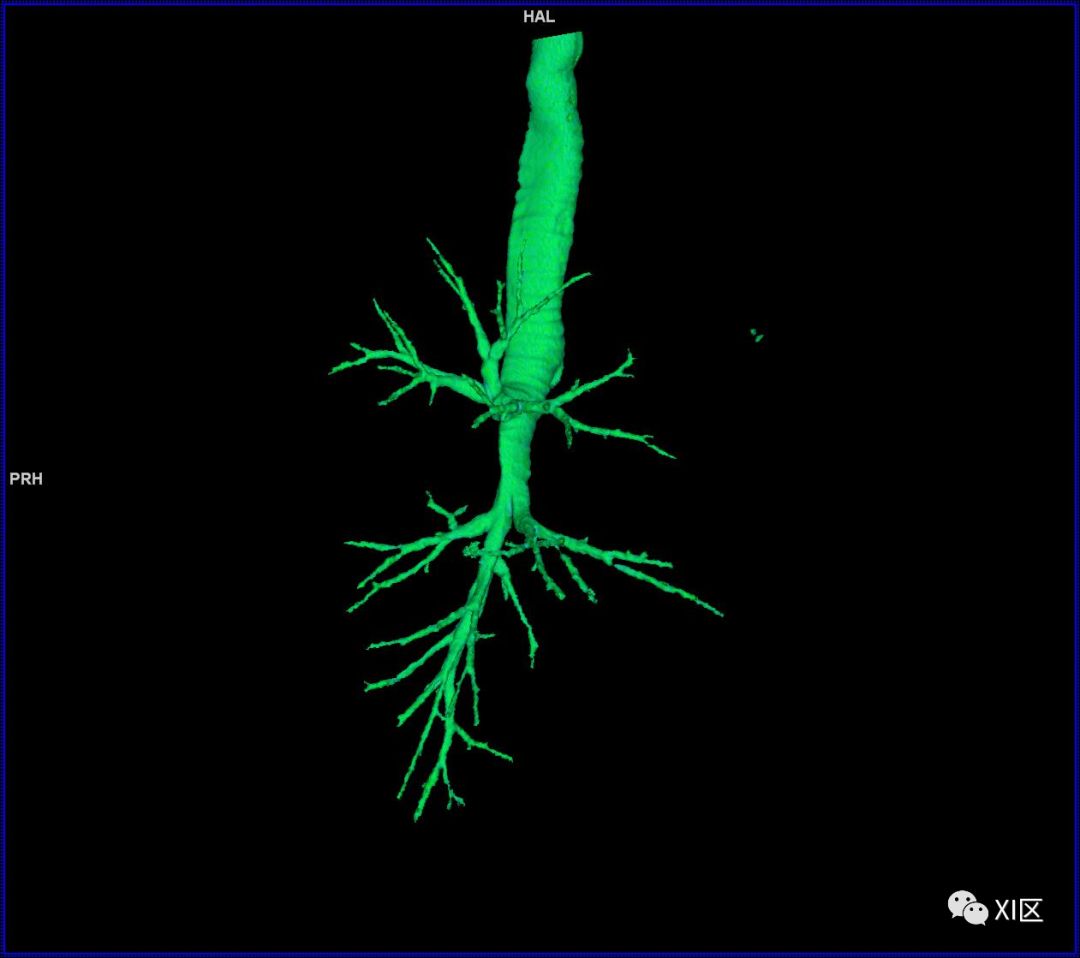

气管树的解剖

人的支气管(第1级)至肺泡约有24级分支。支气管经肺门入肺,分为叶支气管(第2级),右肺3支,左肺2支。叶支气管分为段支气管(第3~4级),左肺8支、右肺10支。段支气管就是肺的分段的依据。段支气管反复分支为小支气管(第5~10级),继而再分支为细支气管(第11~13级),细支气管又分支为终末细支气管(第14~16级)。从叶支气管至终末细支气管为肺内的导气部。终末细支气管以下的分支为肺的呼吸部,包括呼吸细支气管(第17~19级)、肺泡管(第20~22级)、肺泡囊(第23级)和肺泡(第24级)。

气管支气管形如树状,因此也称气管支气管树。

气管树

气管树与左右肺的关系

气管树与胸部其他结构的关系